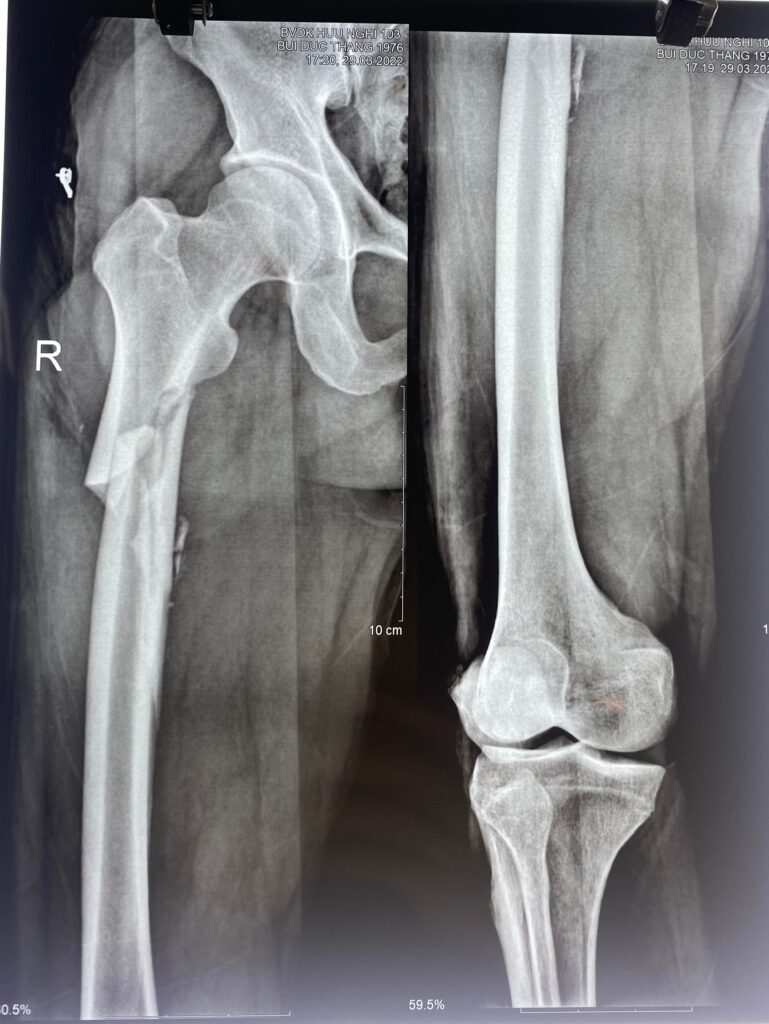

Phẫu thuật xương đùi cho bệnh nhân nam 46 tuổi. Bệnh nhân bị tai nạn giao thông với tình trạng gãy kín 1/3 trên xương đùi phải di lệch, có nhiều mảnh vỡ nhỏ.

Sau hơn 2 giờ tại phòng phẫu thuật, bác sĩ chấn thương chỉnh hình đã phối hợp nhịp nhàng với các bác sĩ chuyên khoa gây mê hồi sức để hoàn thành ca phẫu thuật kết hợp xương cho người bệnh.